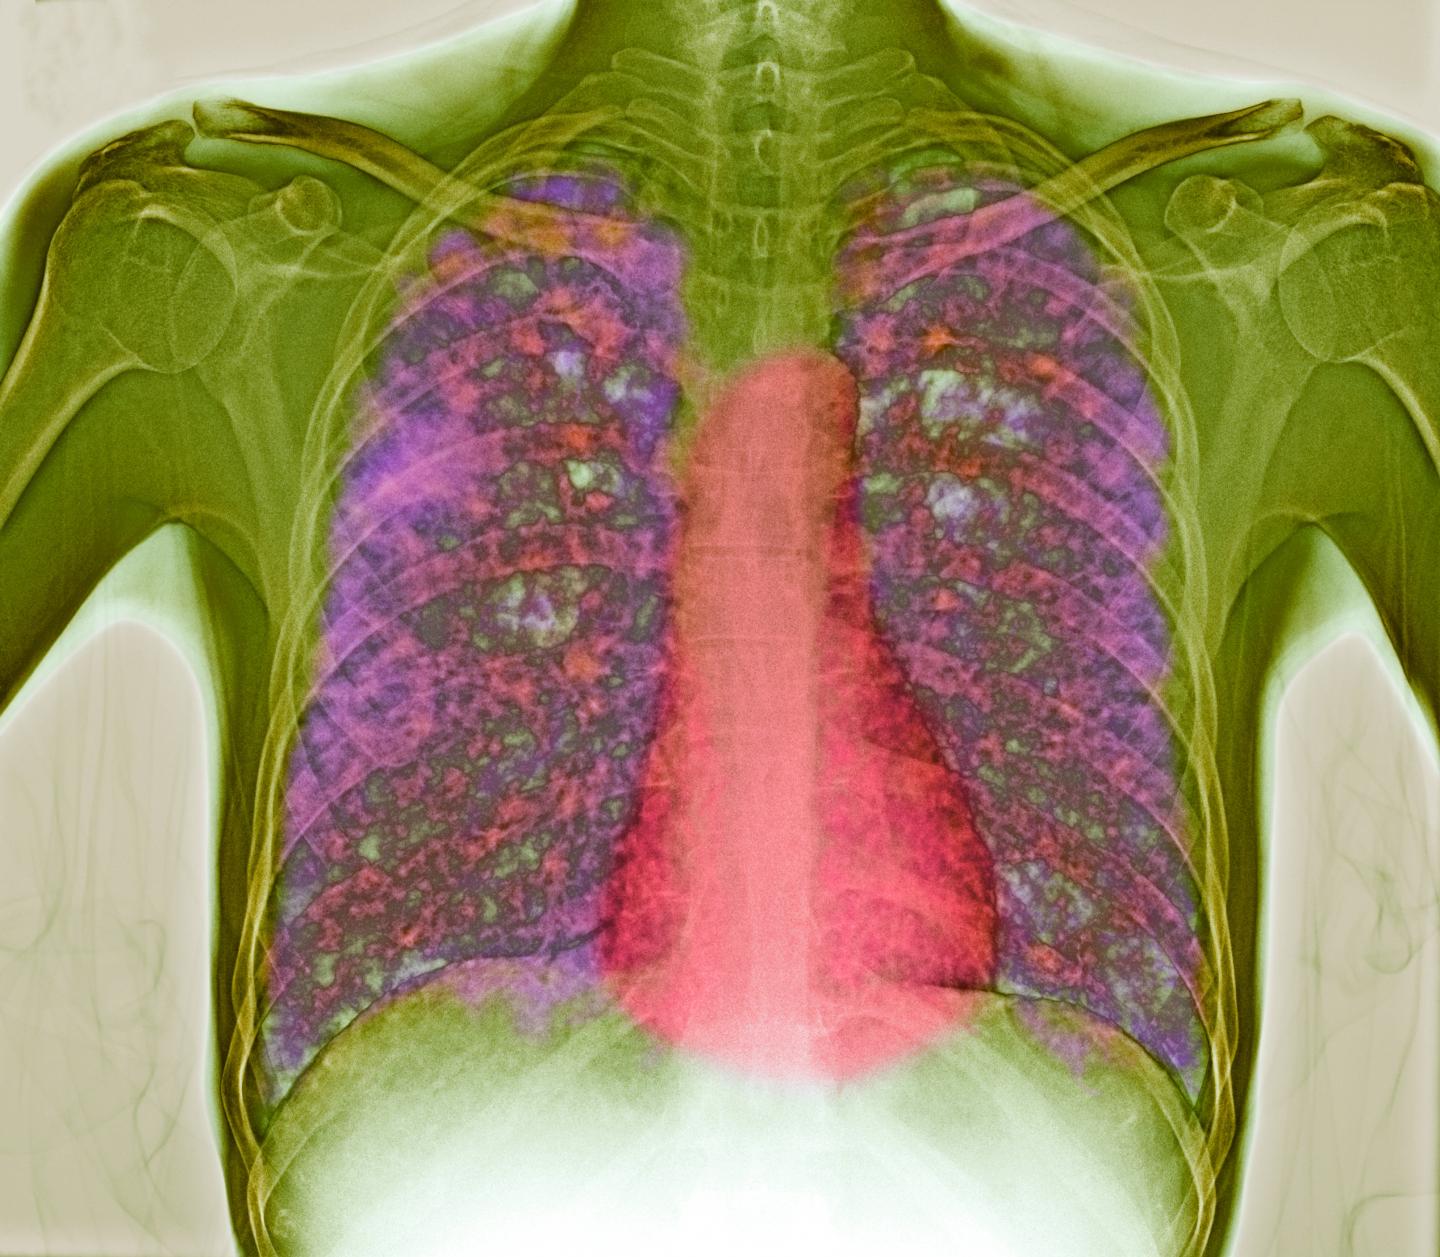

image: This is a colored X-ray of a patient's chest showing disseminated, or miliary, tuberculosis (TB) in the lungs and if left untreated, it has almost 100 percent mortality rate. The lungs contain lesions (tubercles, pink) consisting of infected dead tissue. Using mouse models of TB, Tzelepis et al, have identified the critical role of mitochondrial Cyclophilin D for regulating T cell mediated immunity in disease tolerance independent of host resistance to Mycobacterium tuberculosis.

DU CANE MEDICAL IMAGING LTD/SCIENCE PHOTO LIBRARY